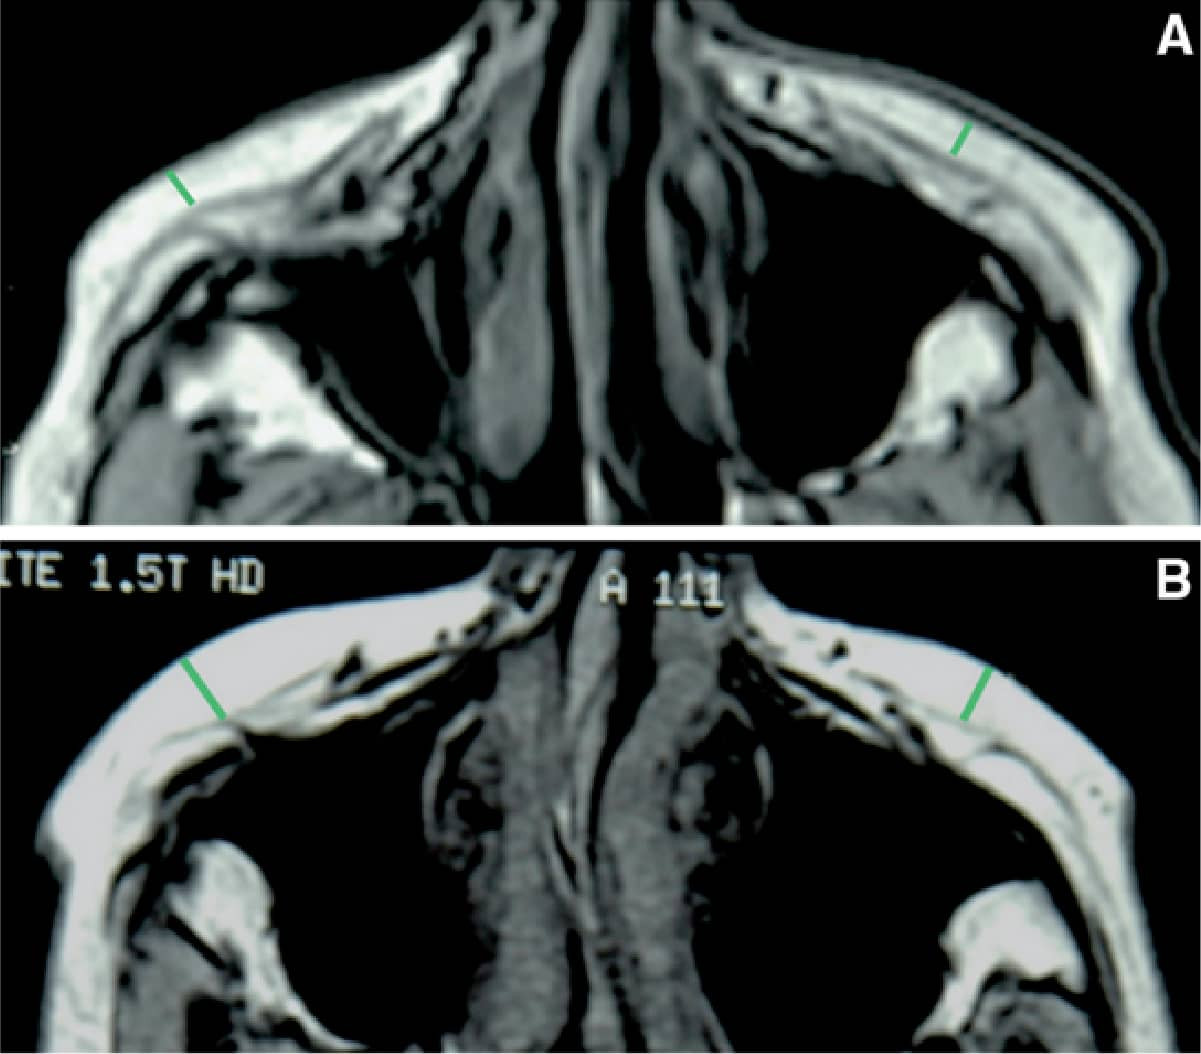

(三)肌肉層:根據核磁共振的研究,年輕面部肌肉因脂肪支撐度較好,水平剖面肌肉呈現微凸形狀(Convexity),老化後肌肉變薄、長度縮短、張力上升、呈現較為直線形狀,這與脂肪支撐下降也有關。

Fig2. 參考來源:Aesth Plast Surg (2012) 36:753–760